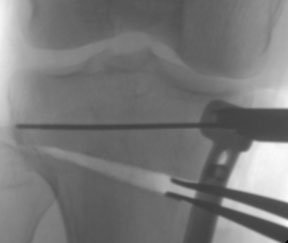

After making the cut with a saw, gradually open up the gap in the bone by using a series of fine chisels. The photograph on the left shows the stepwise insertion of chisels, allowing the cut bone to be wedged open by an exact amount. The X-ray on the right shows that the tibia bone has been cut and wedged open (the wedged-open space shows up dark against the paler surrounding bone). The plate holds the wedge open. So this is a high tibial osteotomy with the opening-wedge technique.

The first small chisel frees the bone and gets the osteotomy mobile, and then the second chisel is introduced alongside it to gradually open up the gap to the point where we sometimes have as many as 4 or 5 chisels in the osteotomy site. This would produce a gap of about 7 mm normally but the gap can be as much as 2 cm.

Once the chisels are taken out the gap in the bone would close, so you need something to open it up again. Here we use laminar spreaders (see X-ray on left) are placed in the osteotomy gap and allow us to adjust the gap correctly to whatever level we want. The amount of "opening" is very accurately calculated by a specially designed computer programme during the planning of surgery that takes place before the osteotomy is carried out.